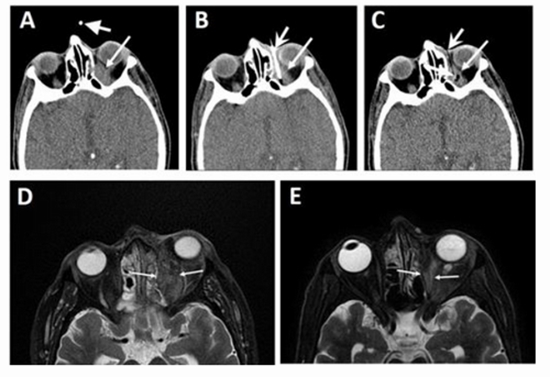

CT Scan Guided Intra orbital Amphotericin Injection in COVID 19 associated Mucormycosis, a pilot study

Purpose : A high incidence of sinu-orbital Mucormycosis as a fulminant and opportunistic fungal infection happened following the COVID-19 pandemic. Traditionally, patients with apical or extensive orbital involvement are candidates for exenteration. We designed and applied CT scan guided orbital amphotericin C delivery. In this study we aimed to report this novel technique and results of this method in control of orbital mucormycosis with apical involvement.

Results : A total of thirty patients with mean age of 52±11.86 were enrolled in this study. Twenty-three (76.7%) patients were male; group A: 11 (73.3%) and B: 12 (80%). The majority of the patients in both group were diabetics (A: 10 (66.7%), B: 10 (76.9%)). Most patients in both groups had received corticosteroids and antiviral therapy for their recent COVID-19, 23 (82.1%) and 25 (89.3%), respectively. No patient in group A underwent exenteration. Eleven (78.6%) patients in group B underwent orbital exenteration. Of the 6 expired patients, 5 (83.3%) were in group B (P<0.0001). Peri-orbital ecchymosis and intracranial air extension were observed in 2 (13.3%) and 1 (6.7%) in group A patients, respectively.

Conclusions : Intra-orbital amphotericin injection under CT-guidance can be considered as a highly effective method in patients with orbital mucormycosis. This method may decrease exenteration without increasing mortality of patient.